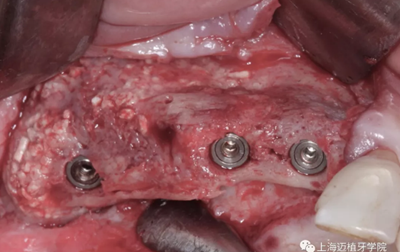

術(shù)前照,生物骨材料植骨失敗,植體暴露,生物骨材料沒有成骨(如圖),垂直向和水平向都受到感染

植體取出后,可以清晰地看到骨粉未成骨,還是顆粒狀